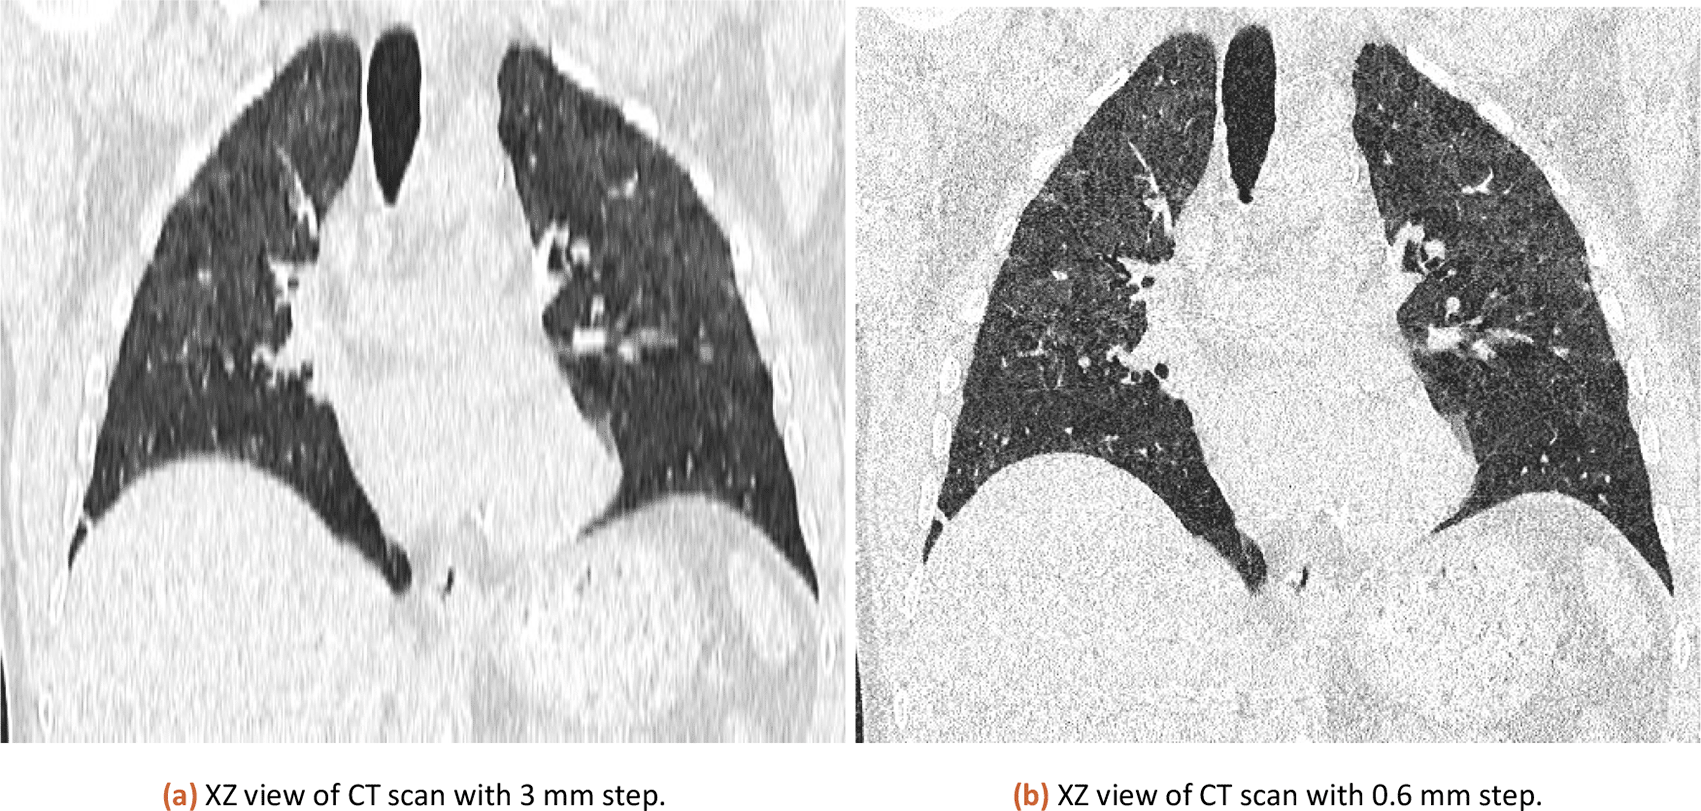

The tool has been tested both 3 mm slicing and 0.6 mm slicing CT images. The results were similar in percentage and the final CT score was the same.

The international standard for saving DICOM files defines 3 mm slicing of CT data as the default way. However resaving data as TIFF (losing voxel information) or using different slice thicknesses (like 0.6 mm slicing) may result in a different result. In theory, 0.6 slicing would provide 5 times more detailed sampling in the Z-axis, however, in practice it is different.

The same CT dataset exported with 0.6 and 3 mm slices (XZ view for comparison is in Figure 3) was analyzed with our tool with a lung threshold of 0-155 and a pneumonia threshold of 47-115. The results can be found in Table 1. The error from a comparison of 3 mm and 0.6 mm slicing is estimated at 0.58 %. The used CT is available in the attached published dataset as CT1_1 (0.6 mm slicing) and CT1_2 (3 mm slicing).